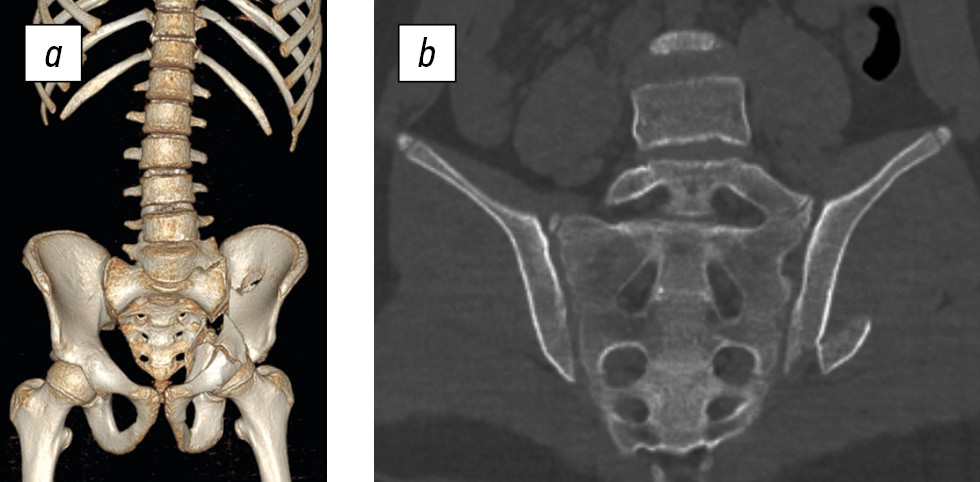

Fig. 2. Three-dimensional reconstruction (a) and CT scan (b) of the lower lumbar spine and sacrum of a 16-year-old female patient. Type a sacral injury (right iliac wing fracture). Transitional lumbosacral vertebra, type III, subtype b.

Analysis of the CT scans shown in Fig. 2 focused on the sacrum, which exhibits five pairs of sacral foramina. Normally, five sacral vertebrae fuse by the age of 22–24 years to form the sacrum (os sacrum), which has four pairs of sacral foramina [12]. A sacrum with five pairs of sacral foramina, as revealed by 3D reconstruction, is an indicator of transitional vertebrae type III or IV [11].